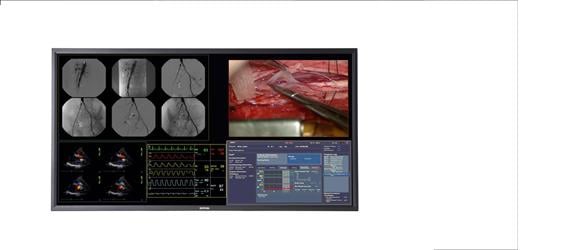

The conferencing system used in Hammersmith combined MultiSense's telemedicine infrastructure with Barco's surgical display technology. The system provided viewers with a real-time, two-way communication link between the operating theater and the conference room, thereby enabling detailed discussions while the procedure was being performed. Thanks to the surgical display's intelligent picture-in-picture functionality, the audience had a high-definition view of the operation on screen, including local and remote camera images, the patient's vital signs, and the endoscopic video of the operation.

“The MultiSense medical cart provides a very efficient and comfortable way of visualizing and sharing images and data, both inside and outside of the surgery suite,” said Dr. Punjabi. “The most important aspect of the solution, however, is the excellent quality of the patient images. The Barco MDSC-2124 surgical display guarantees excellent performance under high ambient light conditions, and allows for detailed discussion during the procedure. Moreover, at 1,920 x 1,200, its high-definition resolution improves depth perception, enhances hand-view coordination and allows for better patient care overall.”